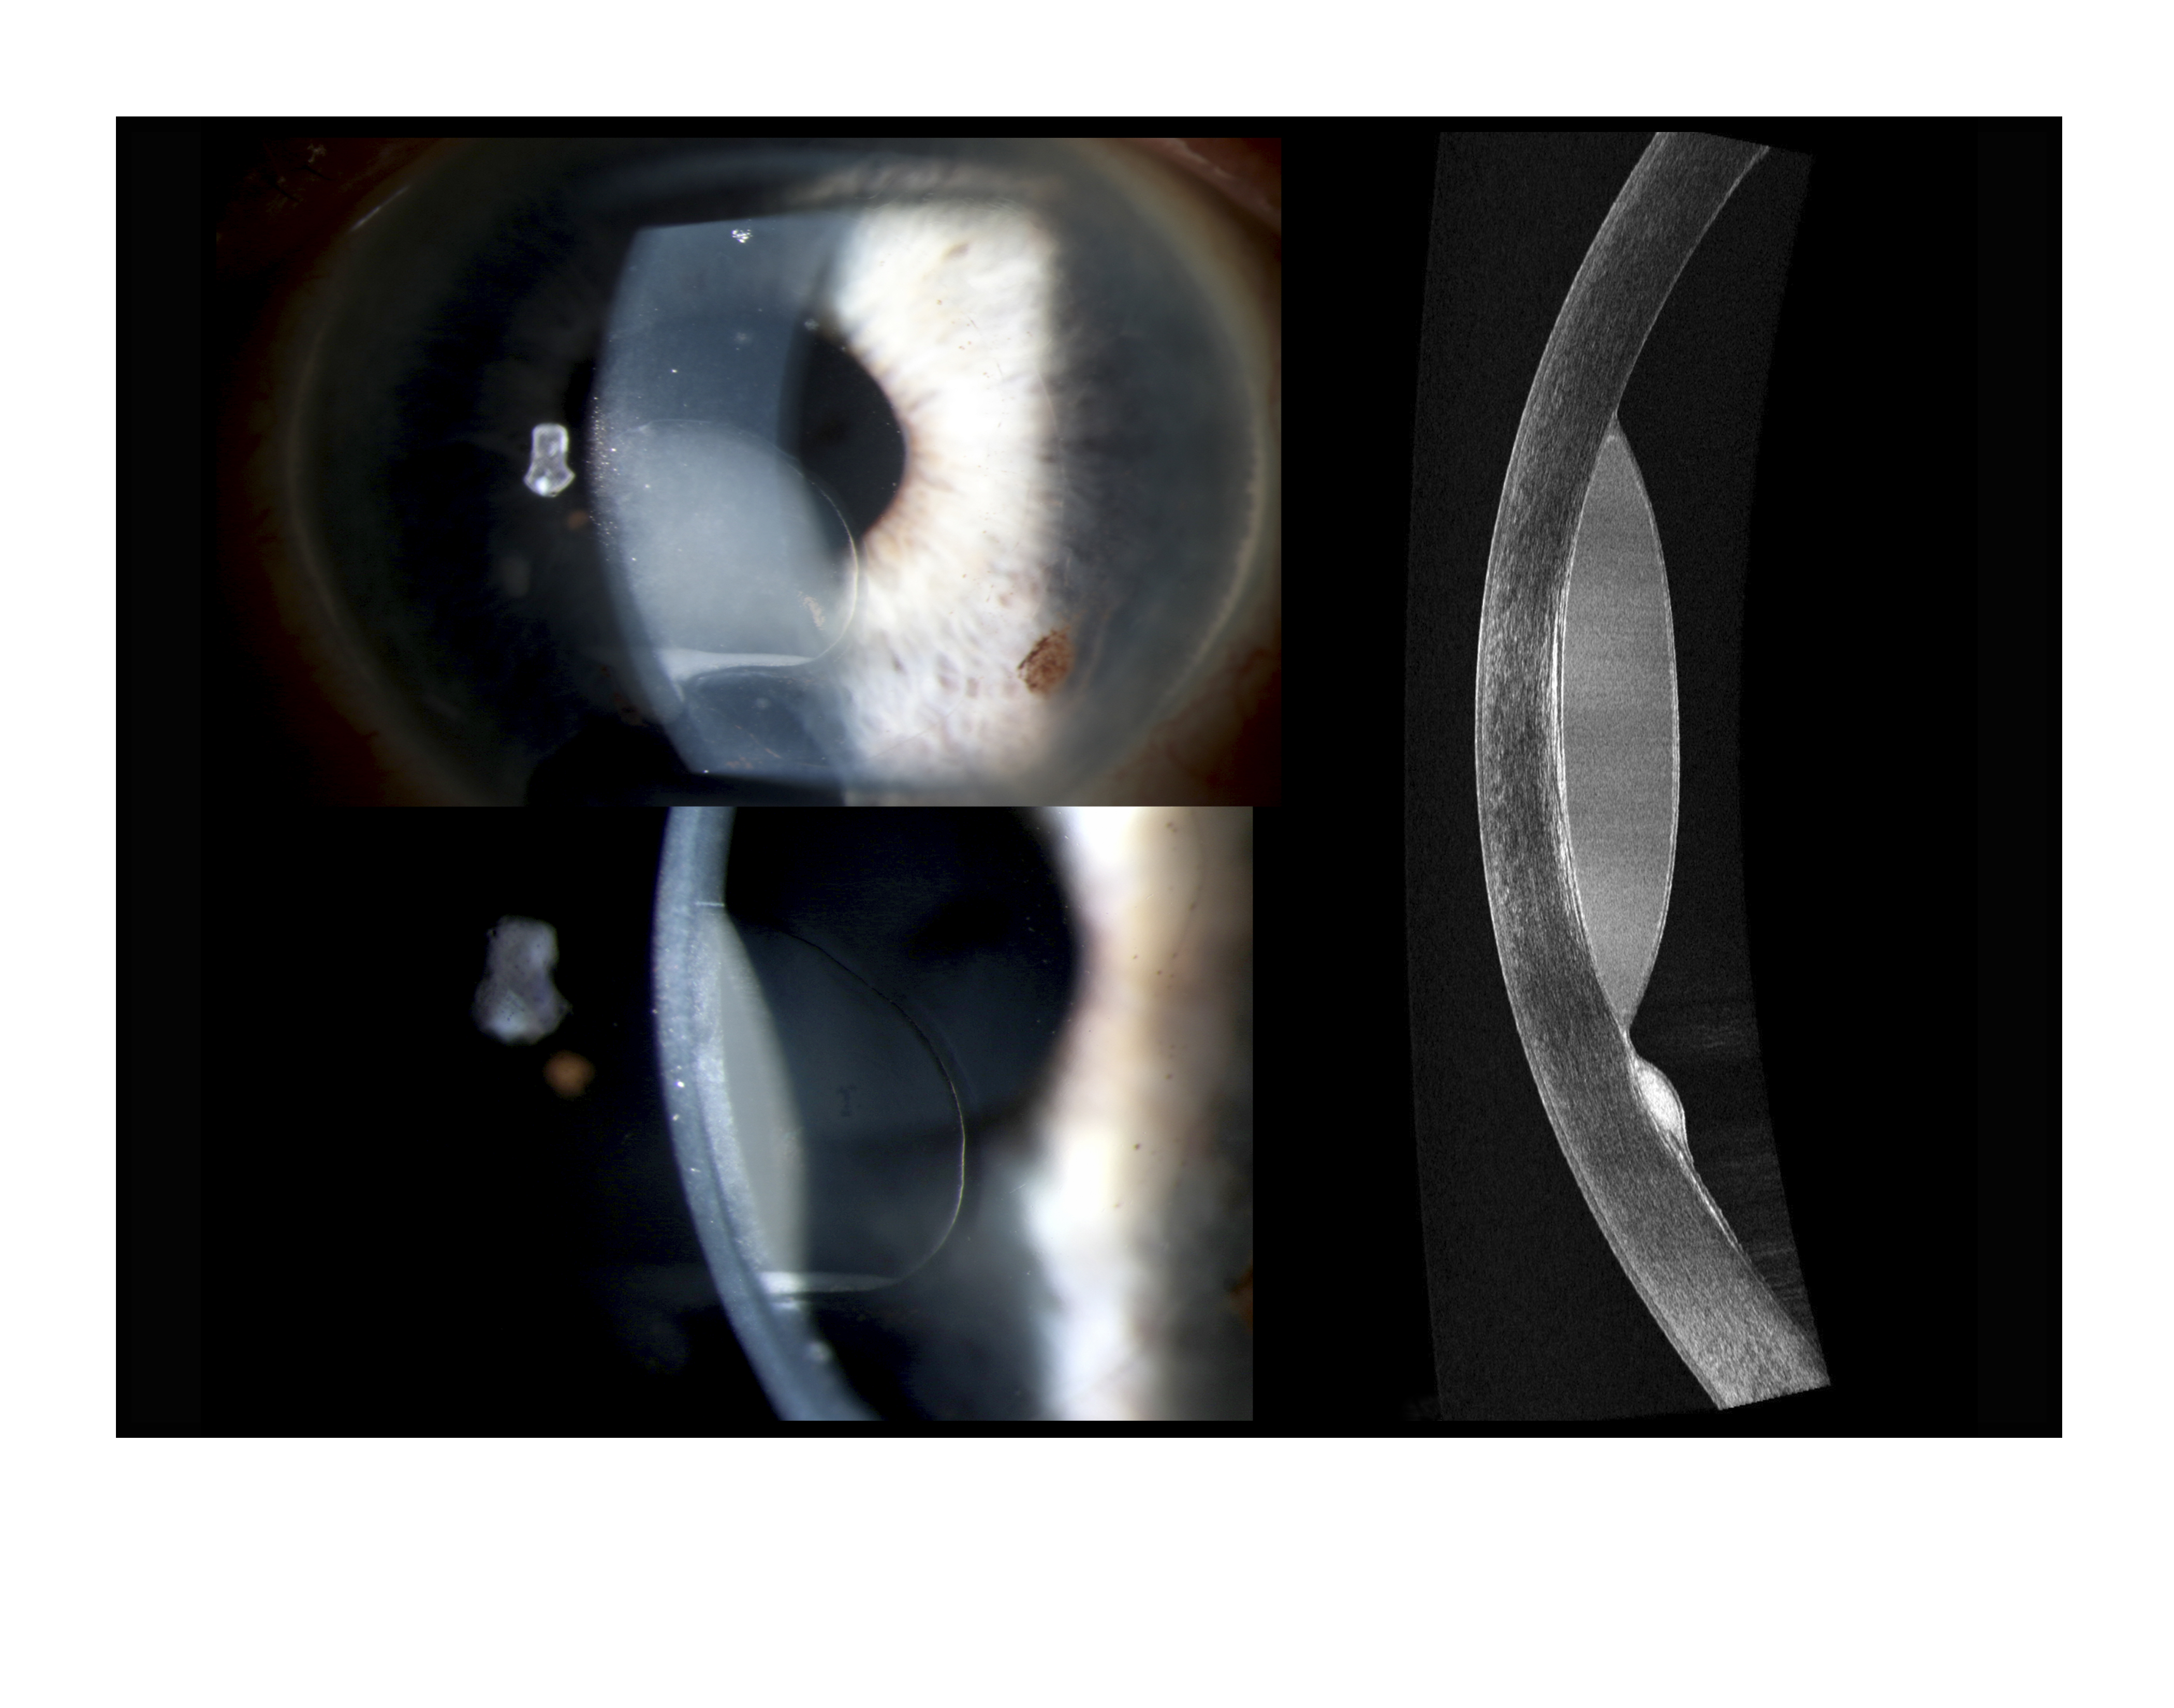

Corneal Epithelial Ingrowth Presented by Mark Harrod, CRA, OCT-C This photograph received Second Place in the category "Cross Categories" and was displayed in the 2024 OPS Exhibit. Filed Under Retina OPS Photo